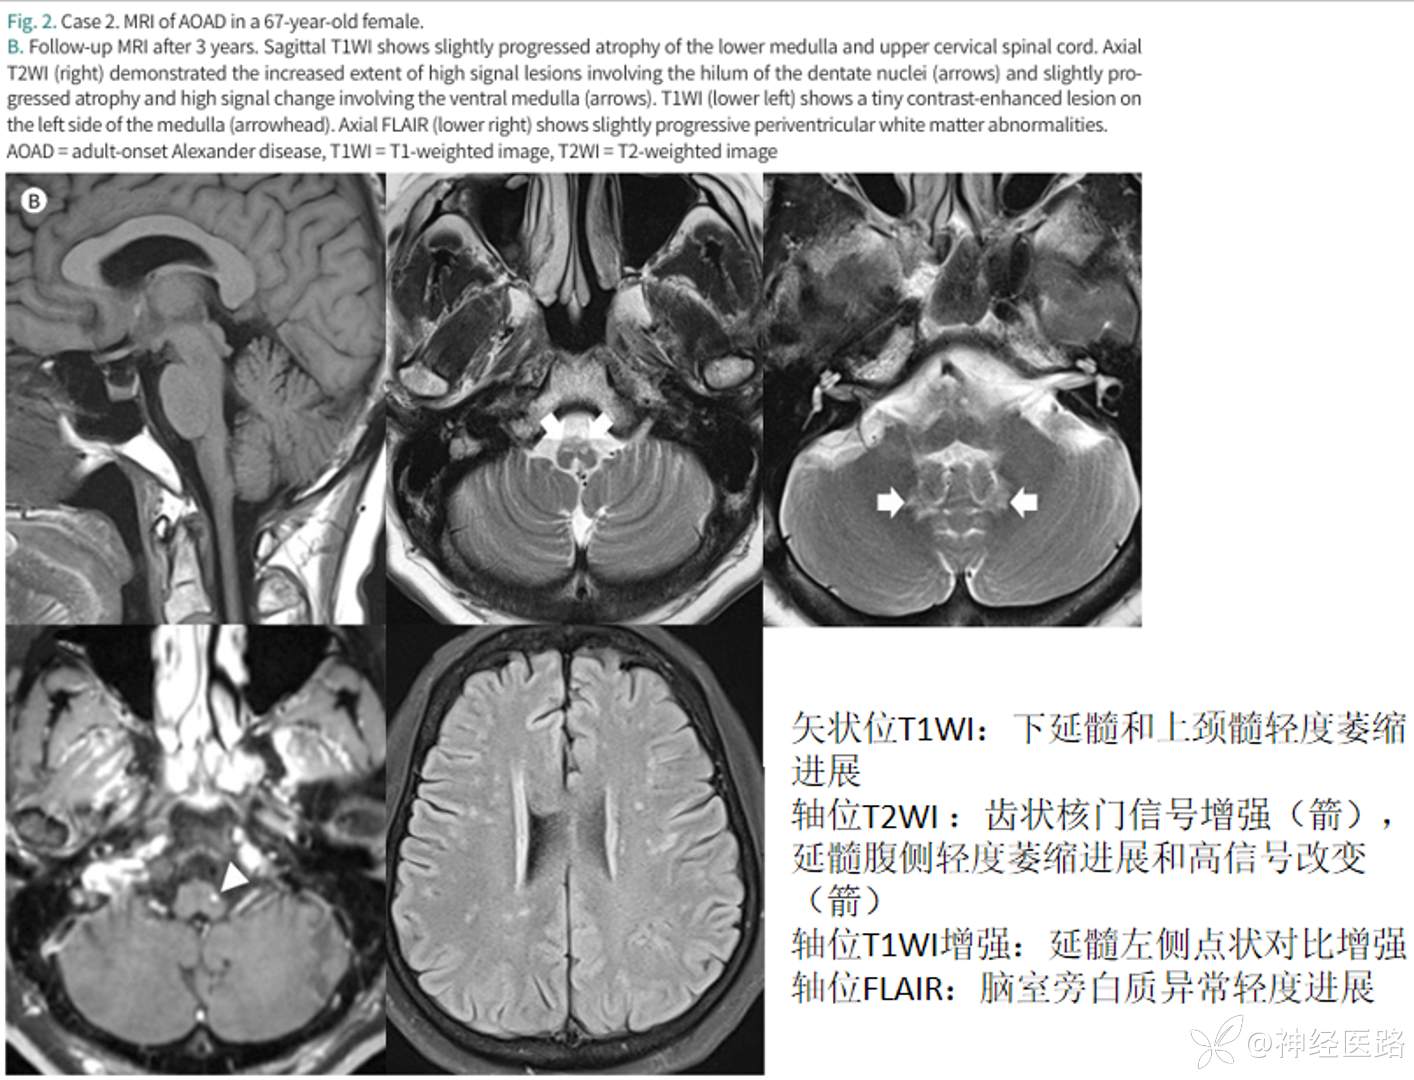

AxD脑磁共振最典型表现是额叶为主的脑白质营养不良,在婴儿型中最为典型。但II型成人多见,影像学表现不典型,幕上脑白质改变不突出,表现为下位脑干至颈髓萎缩,表现“蝌蚪征”。桥臂基本不萎缩。

a:延髓明显萎缩 a、b:小脑轻度萎缩 c:中脑背部萎缩 l:典型的蝌蚪样脑干萎缩(构成包括延髓颈髓明显的萎缩、完整的桥脑基底部)

成人亚历山大病临床表现多样,影像以延髓和高颈髓萎缩为特点。